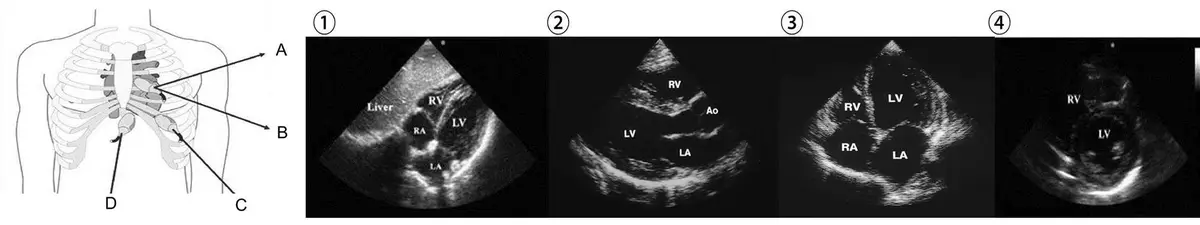

將心臟超音波探頭放置於下圖左邊人型不同位置( A 長軸、 B 短軸、 C 、 D )可分別讀出右邊①②③④何種圖像?

心臟超音波(echocardiography)標準探頭擺放位置與對應影像切面的對應關係,包含胸骨旁長軸(parasternal long axis, PLAX)、胸骨旁短軸(parasternal short axis, PSAX)、心尖四腔(apical 4-chamber, A4C)及肋骨下(subcostal)四個標準視窗。

左側人型示意圖(探頭位置 A、B、C、D):

- A:位於胸骨旁(parasternal),探頭指向較高位置(靠近胸骨第 3-4 肋間),為胸骨旁長軸視窗位置

- B:位於胸骨旁相同肋間,探頭方向旋轉 90°,為胸骨旁短軸視窗位置

- C:位於心尖部(左胸外側偏下,約第 5 肋間,最大搏動點),為心尖視窗位置

- D:位於劍突下(subxiphoid/subcostal),探頭置於上腹部劍突下方,為肋骨下/劍突下視窗位置

右側四幅超音波影像(①②③④):

- ①:可見 Liver(肝臟)位於左上角,右心室(RV)、右心房(RA)、左心室(LV)、左心房(LA)四個腔室清晰,為肋骨下四腔切面(subcostal 4-chamber view)。肝臟作為聲窗(acoustic window)是此視窗